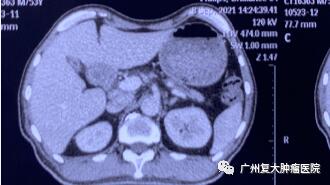

为求进一步诊疗,2020年11月,患者来广州复大肿瘤医院就诊。入院完善相关检查发现:CA-199指标高达2289u/ml(CA-199属胃肠道肿瘤相关抗原,是一种肿瘤标志物,正常值≤37u/ml);肝实质内有多个结节状,较大者约4.3×3.8cm。胰腺体、尾部均有肿块,并邻近肠管、脾静脉局部粘连不清,大小约4.3x3.3cm。

影像图片显示

图2